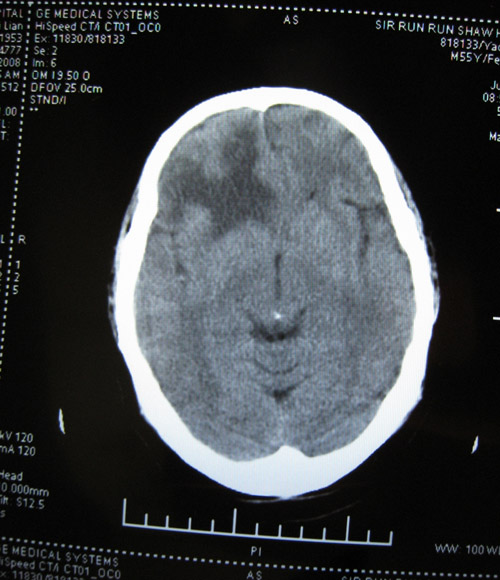

CTʱ¼ä2008-07-15 ÔçÉÏ9µãÖÓ

CT±¨¸æ

ÓÒ²à¶îÒ¶¼ûÇ·¹æÔòÍÅÆ¬ÉÔ¸ßÃܶÈÓ°£¬ÆäÖܱ߼ûƬ״µÍÃܶÈÓ°Ë®Ö×Ó°»·ÈÆ£¬±ß½çÇ·Ç壬¾Ö²¿¿É¼ûռλЧӦ£¬ÓÒ²à¶îò¨Ò¶ÄÔ¹µ±ädz£»ÓàÄÔʵÖÊÄÚδ¼ûÒì³£ÃܶÈÓ°£¬ÖÐÏßÏò×ó²àÒÆÎ»£¬Â¹Çδ¼ûÃ÷ÏÔ¹ÇÕÛ¡£

ÎÊÌâ²¹³ä£ºCTƬ2008-07-15 µÄÓ¡ÏóÊÇ£ºÓÒ²à¶îÒ¶ÄÔ´ìÁÑÉ˰éѪÖ×Ðγɣ¬¶ÔÕÕ08.07.09ƬѪÖ×ÉÔÎüÊÕ£¬Ë®Ö×Ïà·Â¡£